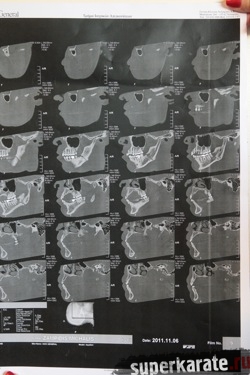

Обследование, проведенное в одной из лучших клиник города Афины квалифицированными греческими специалистами, прошло при участии официальных представителей Майка Замбидиса, мировой версии W5 и Московского общества греков. В рамках обследования Майку Замбидису был сделан рентгеновский снимок черепа, после чего снимок был подвергнут тщательному изучению. Также была проведен визуальный осмотр полученной травмы.

В результате полученных данных был сделан однозначный вывод о том, что Майк Замбидис действительно получил перелом нижней челюсти с левой стороны, и что дальнейшее продолжение боя могло привести к серьезным последствиям для здоровья Замбидиса.